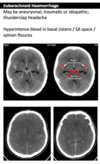

Subdural on CT head

143

Extradural on CT head

144

Subarachnoid haemorrhage on CT head

145

SAH